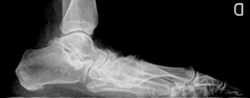

Es una alteración de la estructura normal del pie. El pie tiene una bóveda plantar fisiológica que es la adecuada para la función de soporte y marcha. Cualquier alteración de la estructura distorsiona el funcionamiento normal del pie y puede producir dolor.

Hay múltiples causas. Las principales deformidades son: pie equinocavovaro, pie plano y pie cavo. En los niños la causa más frecuente es la congénita. El pie plano del adulto se produce principalmente por la rotura del tendón tibial posterior. Los pies cavos aparecen por una alteración neurológica. El primer consejo que damos a nuestros pacientes es utilizar plantillas o férulas para corregir la deformidad o repartir las cargas anormales.